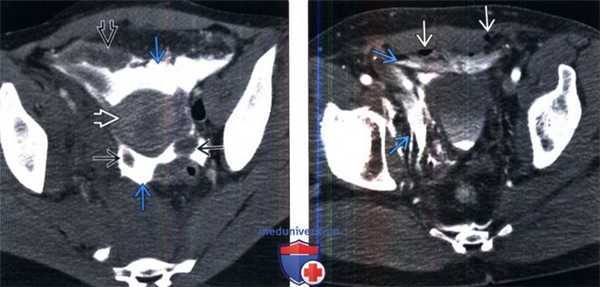

(Слева) КТ с контрастированием после цистографии, аксиальный срез: экстравазат контрастируемой мочи, окружающий матку, яичники и петли тонкого кишечника. Эти признаки характерны для внутрибрюшинного разрыва мочевого пузыря.

(Справа) КТ с контрастированием после цистографии, аксиальный срез: экстравазат контрастируемой мочи в околопузырных пространствах, вследствие внебрюшинного разрыва мочевого пузыря. Визуализируются несколько пузырьков газа глубоко в прямых мышцах живота, вследствие травмы мягких тканей и перелома таза.

(Слева) КТ с контрастированием, аксиальный срез: диастаз лобкового симфиза и скопление жидкости в мягких тканях спереди; зачастую затруднительно определить, является ли это скопление мочой или гематомой, или и тем, и другим.

(Справа) Контрольная цистография, передняя проекция: у этого же пациента определяется экстравазация контраста из мочевого пузыря в ткани внебрюшинного пространства, окружающие мочевой пузырь, а также вдоль верхней трети левого берда и мошонки. Небольшое количество контраста определяется в мочевом пузыре. (Слева) КТ с контрастированием, выполненная для оценки первичной травмы, аксиальный срез: околопузырное скопление жидкости. Дифференциальный диагноз включает скопление мочи или крови. Небольшое кровотечение заметно в подкожной клетчатке спереди и в околопрямокишечном пространстве.

(Справа) КТ-цистография, аксиальный срез: у того же пациента выявлено, что околопузырное скопление жидкости является экстравазатом контрастируемой мочи, вследствие внебрюшинного разрыва мочевого пузыря. Обратите внимание на внебрюшинное скопление контраста в околопузырных пространствах, которое имеет форму моляра.